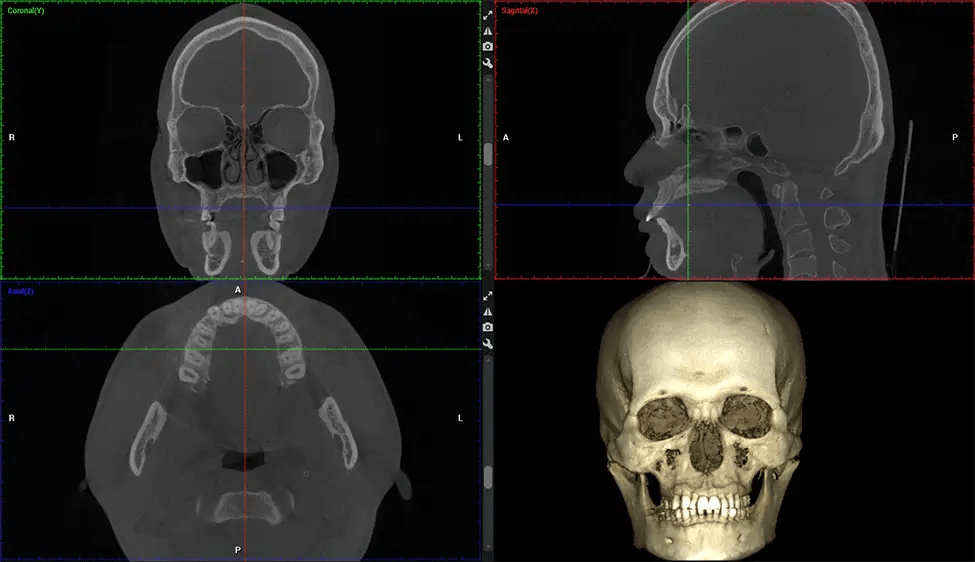

Planmeca Viso G7 CBCT ( Cone Beam CT Scan ) is designed to surpass the demands of industry leaders, specialists, and large institutions. It’s has a large ø25×30 cm sensor with four built-in cameras. It can capture unlimited volume sizes from a ø3×3 cm to a ø30x30cm volume capturing the skullcap through C7 on the cervical spine. The Planmeca Viso G7 offers the industry’s largest single volume scan of ø30×19 cm. It’s poised to handle advanced imaging modalities such as Planmeca ProFace® and Planmeca 4D™ Jaw Motion technology. The occipital head support allows an unimpeded view of facial tissue.

Planmeca is the only manufacturer clinically proven to dramatically reduce patient radiation without sacrificing image quality. Planmeca Ultra Low Dose™ achieves an average reduction in dose of 77% without a statistical reduction in image quality allowing doctors to incorporate 3D imaging into routine protocols with effective patient radiation often lower than 2D intraoral imaging. This increases patient care, allows doctors to diagnose more dentistry, and often earlier in disease progression, than with 2D imaging alone.

Planmeca 3D units also include the industry’s only patient motion detection and correction technology, Planmeca CALM™. This technology corrects movement during CBCT acquisition reducing the risk of retakes.